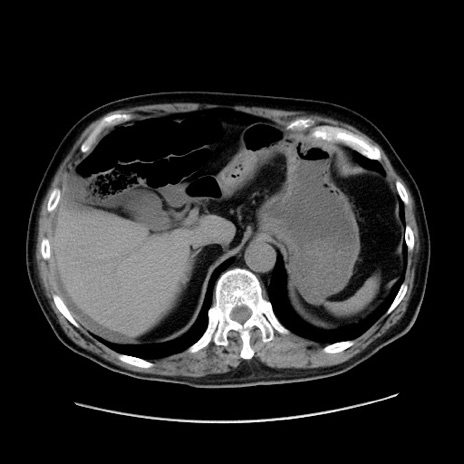

症例30(横断像)

【症例】80歳代男性

【主訴】臍周囲痛

【現病歴】約6時間前から臍下部痛が出現。次第に腹部膨隆・背部痛も生じてきたため来院。背部痛の場所は変化しない。

【身体所見】意識清明、BT 36.3℃、BP  131/87mmHg、P 87bpm、SpO2 100%(RA)、臍周囲自発痛・圧痛あり、反跳痛なし、自発痛部位に一致して板状硬あり、腹部膨隆、腸雑音減弱、CVA tenderness両側陰性。

【データ】WBC 19600、CRP 0.33